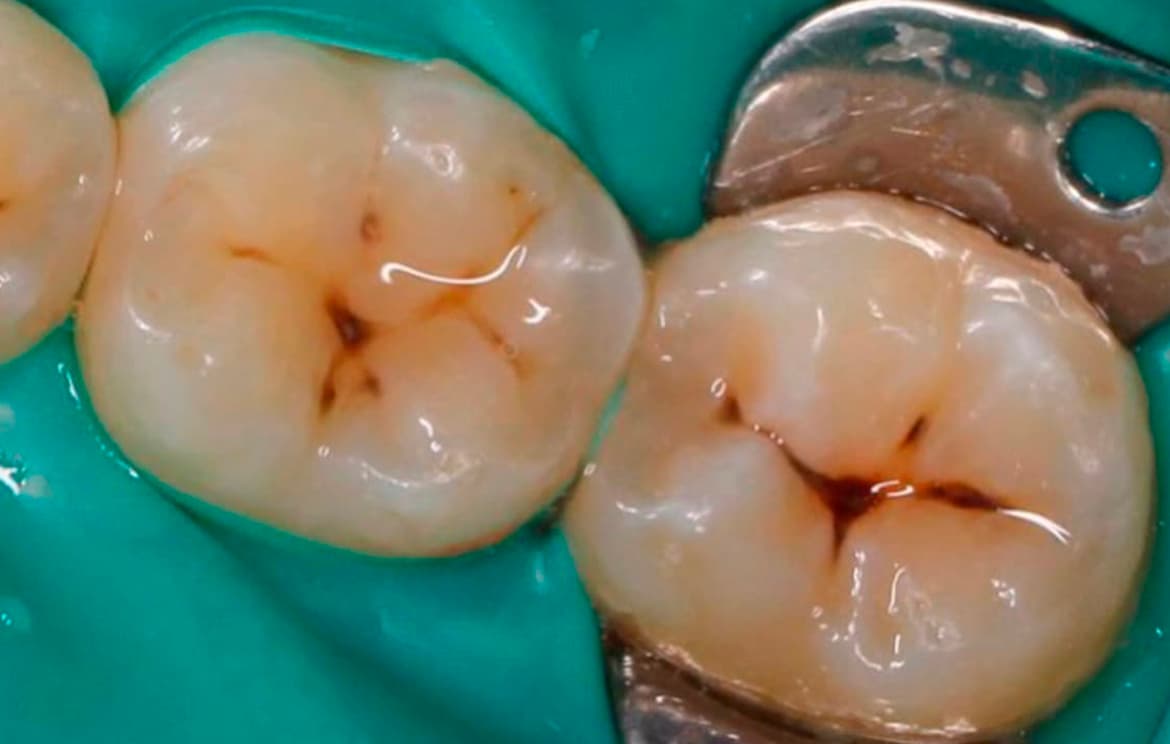

Наши работы